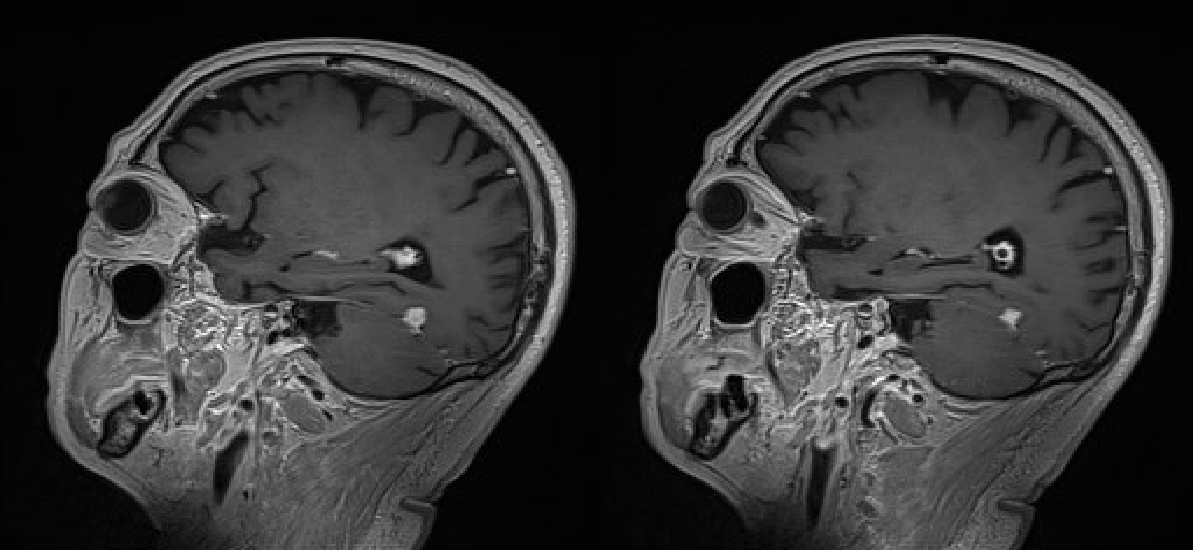

2024年2月,患者因言语错乱来院完善颅脑增强MR(图6):双侧放射冠区多发缺血灶;左侧小脑幕上异常信号灶,考虑脑膜瘤。患者因间断背部疼痛,院外口服"羟考酮20mg q12h、普瑞巴林75mg bid"治疗。